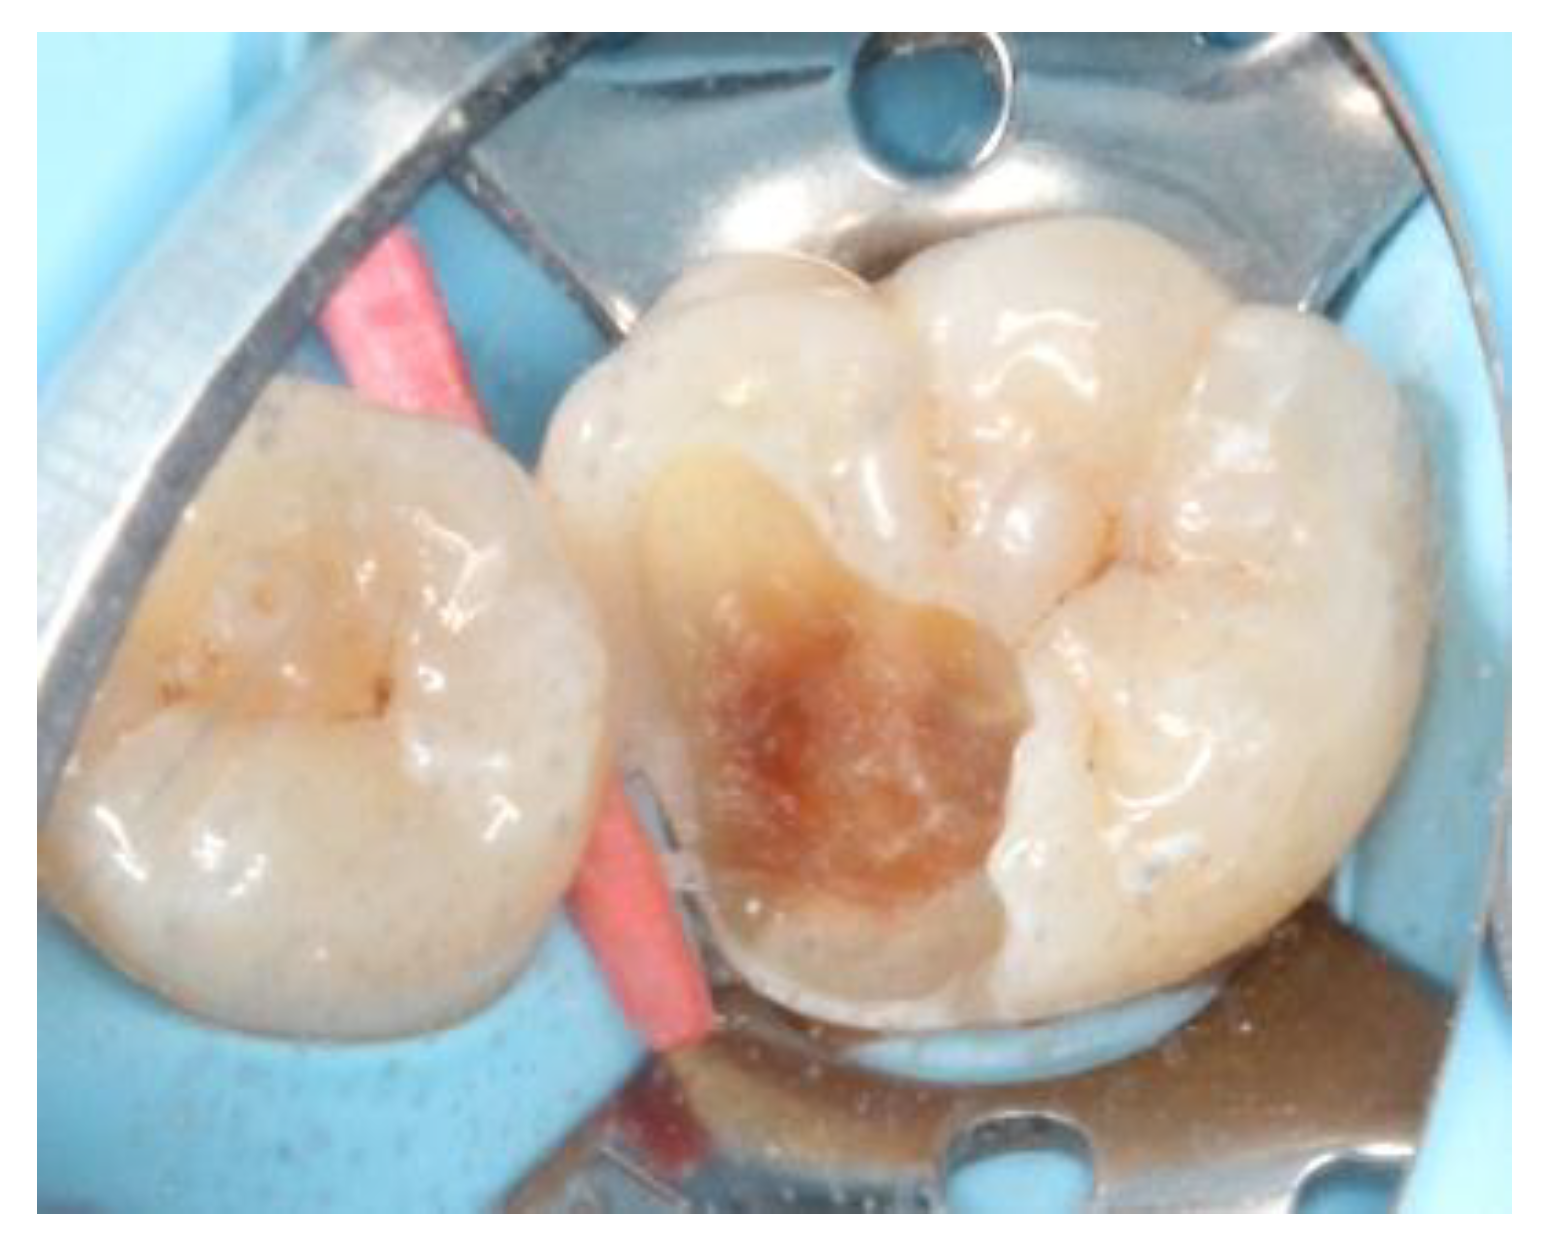

At the next appointment, under block anesthesia using 2% lidocaine with epinephrine 1:100,000, caries was removed by low speed carbide burs and sharpened spoon excavator under rubber dam isolation (

Figure 3). The mesial gingival margin was located approximately 0.5 mm subgingivally. Therefore, gingival displacement was achieved using a retraction cord. The undercuts of the tooth cavity were blocked out with a nano-hybrid composite resin (Grandio, shade A3, Voco, Cuxhaven, Germany), which served as a base material. The cavity was prepared, and an alginate impression was taken after removal of the rubber dam. A self-cured bis-acrylic resin (Structur 2 SC, Voco, Cuxhaven, Germany) was used as a temporary filling material before the next cementation appointment. A fast-setting silicone die material (GrandioSO Inlay System, Voco, Cuxhaven, Germany) was injected into the alginate. During the inter-appointment period, the onlay restoration was fabricated incrementally with a light-cured composite resin (Grandio, shades A2, A3, and A3.5, Cuxhaven, Germany) (